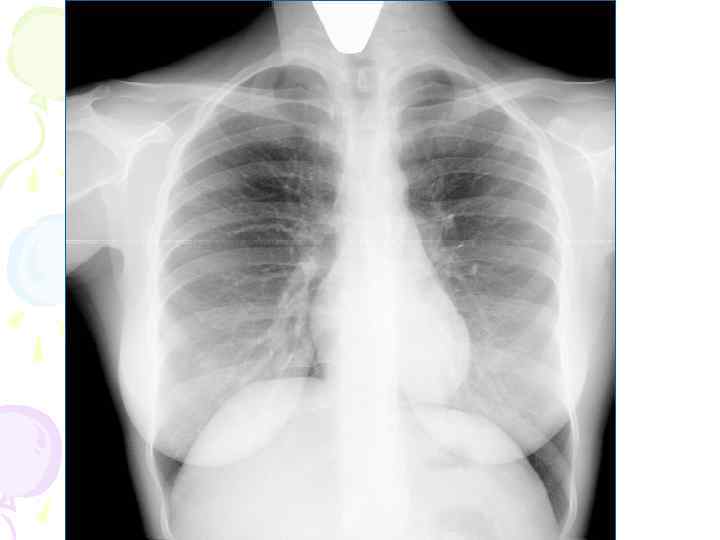

Рентгенологическая картина Спустя 10 -14 дней болезни появляются множественные мелкие / до 2 мм/ однотипные очаги на всем протяжении легких, создается впечатление о более массивной диссеминации в средних отделах. Очаги округлой формы, малой интенсивности, контуры нечеткие, часто расположены в виде цепочки вдоль сосудов. Сосудистый рисунок обеднен

Рентгенологическая картина • множественные крупные / до 10 мм/ однотипные очаги преимущественно в верхних и средних отделах легких • Очаги округлой формы, малой и средней интенсивности, контуры нечеткие, часто расположены в виде цепочки вдоль продольных сосудов • Сливаясь, очаги образуют фокусы затемнения с участками просветления (распад) • При распаде в нескольких отдельных очагах формируются кольцевидные тени – штампованные каверны • При лимфогенной диссеминации очаговые тени с одной стороны, в средних и нижних отделах на фоне лимфангита, в корне кальцинаты

Рентгенологическая картина • Наблюдается полиморфная картина: очаги различной величины, формы и интенситвности, свежие и старые на фоне фиброзных изменений, больше в верхних отделах • Тенденции к слиянию очагов нет • Нарушается симметричность поражения • Могут наблюдаться как тонко- так и толстостенные каверны • Верхушки - интерстициальный фиброз, уменьшение объема, плевральные наложения, в нижних отделах - викарная эмфизема. С-м плакучей ивы. • Тень сердца сужена, имеет срединное положение (капельное сердце) • Фиброз и эмфизема обуславливают деформацию бронхиального дерева, что способствует развитию бронхоэктазов